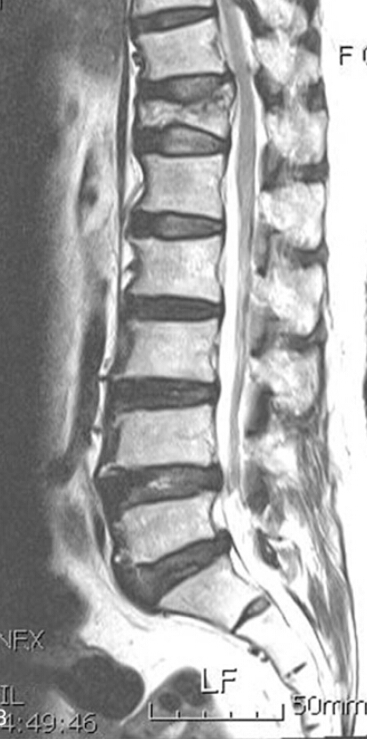

Based on this image, does this patient have a new or old fracture?

old fracture (black is whack, white is right)